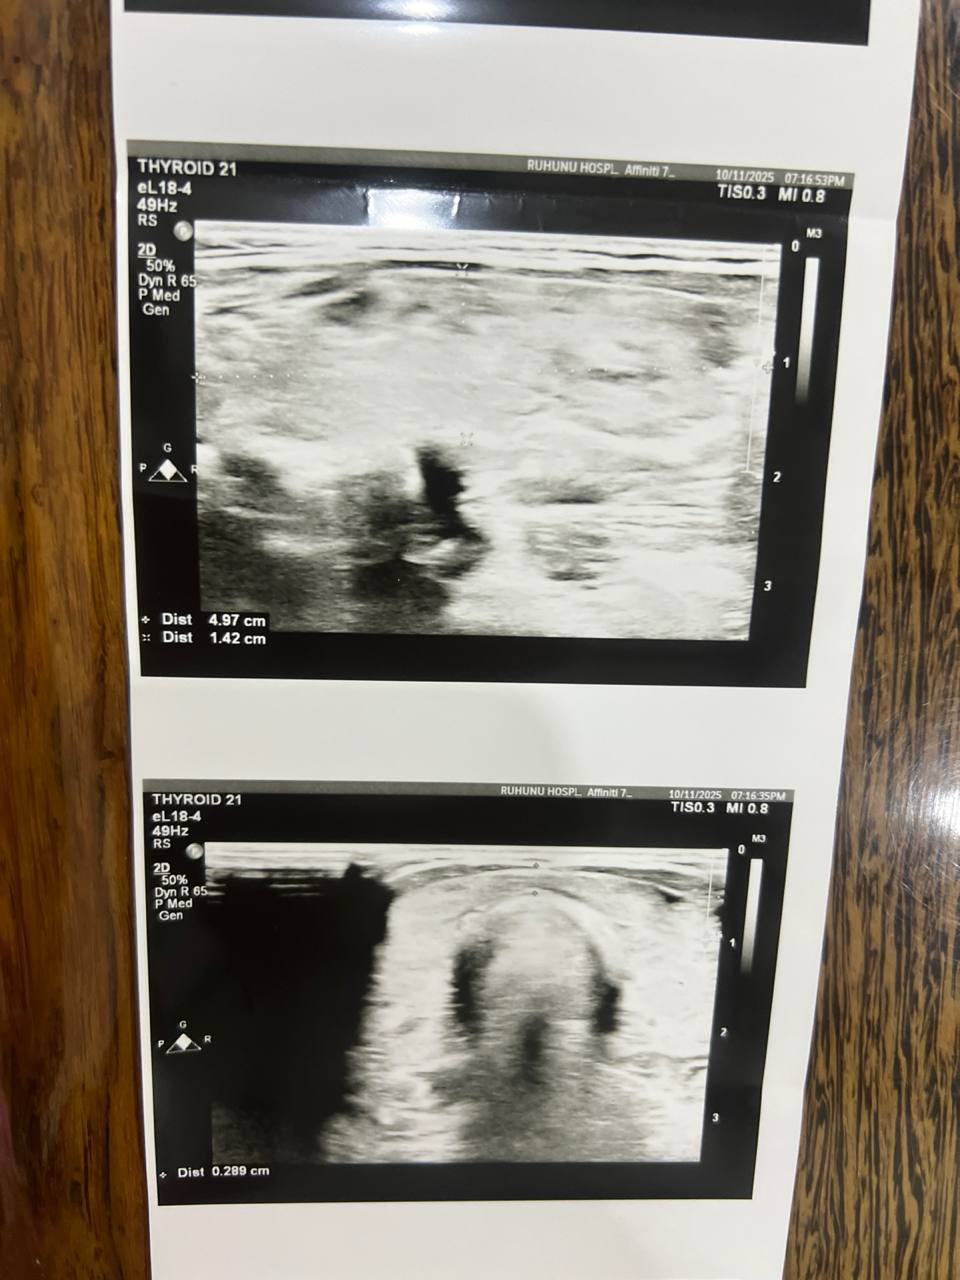

Недавно я сделала УЗИ щитовидной железы:

Незначительное увеличение правой доли щитовидной железы.

Правая доля: 5 см × 1,4 см × 2,2 см

Левая доля: 3,6 см × 0,8 см × 2 см

Очаговых узлов и зоба нет.

Узи расшифровал обычный врач не эндокринолог, вы разбраетесь в снимках? Скажите, подалуйста, на них соответствует картина действительности 65985464.jpg

| Vitaly, здравствуйте! Можете не сомневаться в точности диагноза аутоиммунного тиреоидита, он подтверждается у вас всеми признаками: УЗИ картиной, повышенным титром антител против щитовидной железы, наличием гипофункции - гипотиреоза. Когда начнете лечение гипотиреоза, нужен контроль ТТГ и Т4св через 2-3 мес. для коррекции дозы. Когда доза будет подобрана правильно, можно будет контролировать только ТТГ (TSH) 1 раз в 6 мес. Контролировать и вообще проверять в дальнейшем антитела не требуется, особенно TSH receptor antibodies У вас есть недостаточность витамина Д и железодефицит, рекомендую их устранить приемом витамина Д (в зависимости от веса, не менее 5-7000 IU витамина Д в сутки на 2 мес, затем перейти на поддерживающие дозы - 2000 -2500 IU длительно). И также нужен препарат железа. Контроль ферритина через 1,5-2 мес (цель - выше 50-60). Контроль витамина Д не нужен, анализ не является достоверно точным. Вы можете совместно принимать и левотироксин (гормон), и витамин Д, железо, селен, омега, но не комбинировать одновременно данные БАДы с тироксином (он отдельно принимается, строго натощак утром). Магний можно пропить позже, по окончании приема железа, они мешают усвоению друг друга. Кальций у вас в норме. Изолированное повышение MPV само по себе ни о чем не говорит, если остальные индексы тромбоцитов в норме.